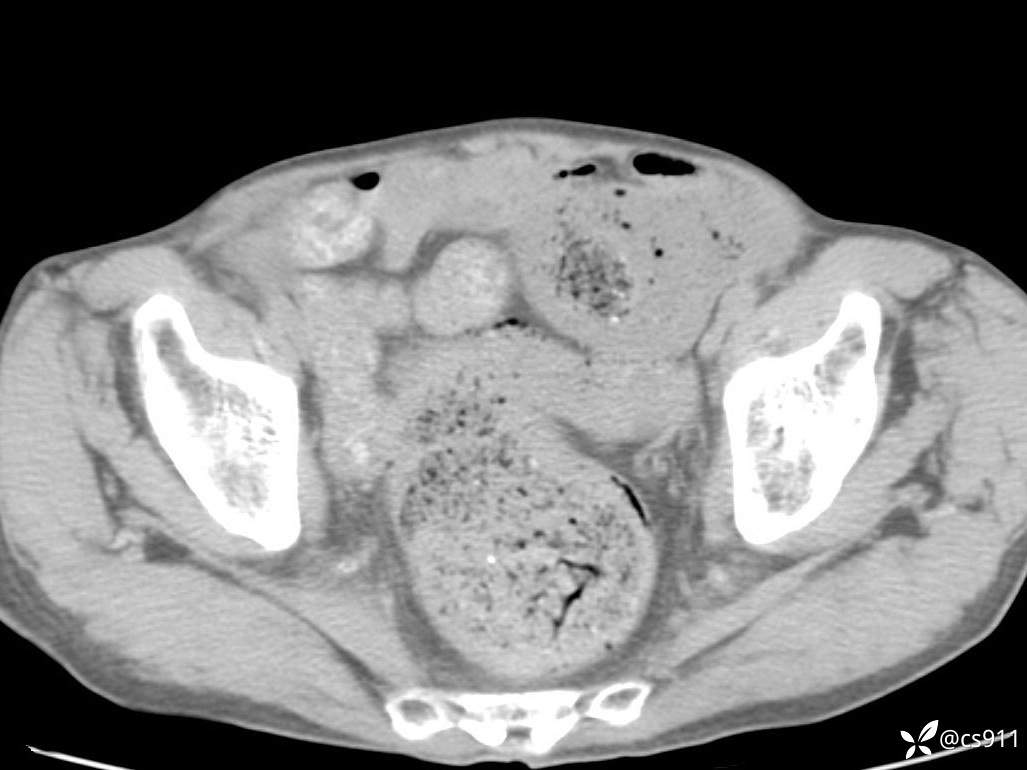

急腹症之急诊CT,原因?答案公布

男,77岁,腹痛、腹胀伴恶心呕吐1天。呕吐胃内容物,非喷射性呕吐,有咖啡色样胃内容物,诉有胃穿孔病史。查体:全腹平,下腹部压痛,全腹无反跳痛,叩诊呈浊音,移动性浊音阴性,肠鸣音减弱,1-2次/分。肛检:直肠未扪及明显肿物,可触及大量粪块。

血淀粉酶(AMY) HH 1859 U/L 35-135

癌胚抗原(CEA) H 27.44 ng/ml 0-5